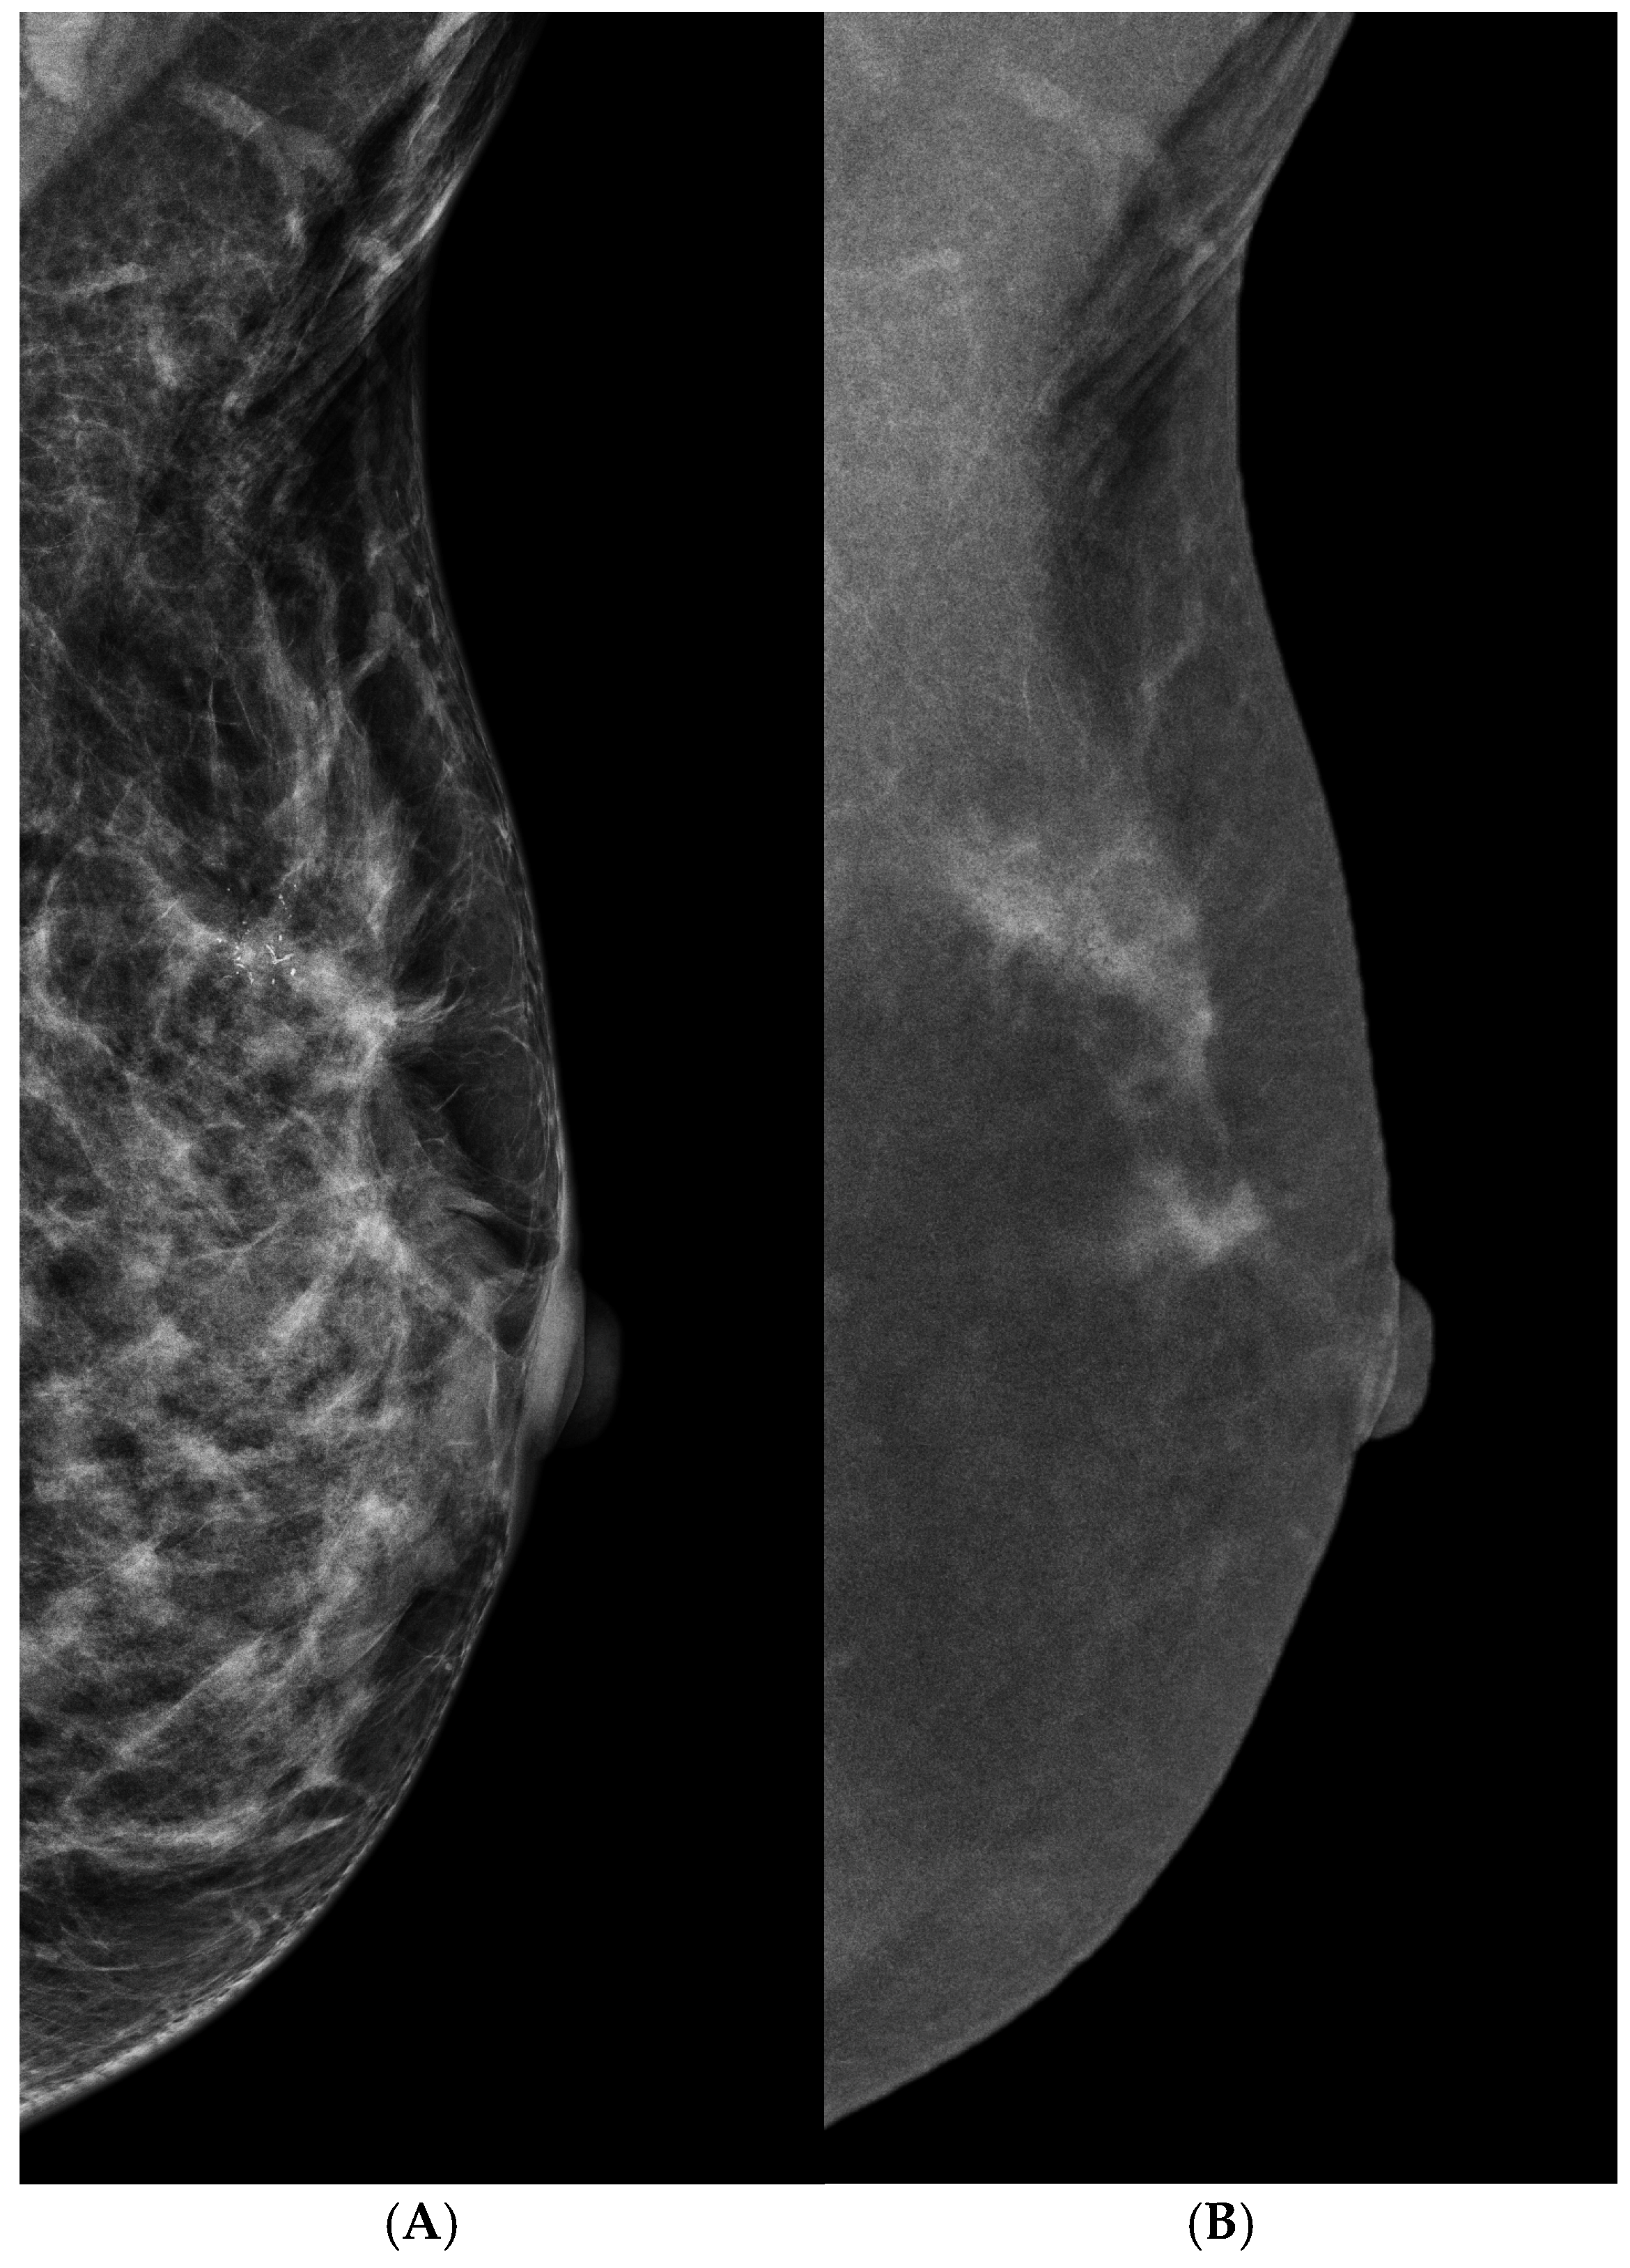

- Bahl, M.; Baker, J.A.; Kinsey, E.N.; Ghate, S.V. Architectural Distortion on Mammography: Correlation With Pathologic Outcomes and Predictors of Malignancy. AJR Am. J. Roentgenol. 2015, 205, 1339–1345. [Google Scholar] [CrossRef]

- Choudhery, S.; Johnson, M.P.; Larson, N.B.; Anderson, T. Malignant Outcomes of Architectural Distortion on Tomosynthesis: A Systematic Review and Meta-Analysis. AJR Am. J. Roentgenol. 2021, 217, 295–303. [Google Scholar] [CrossRef]

- Walcott-Sapp, S.; Garreau, J.; Johnson, N.; Thomas, K.A. Pathology results of architectural distortion on detected with digital breast tomosynthesis without definite sonographic correlate. Am. J. Surg. 2019, 217, 857–861. [Google Scholar] [CrossRef]

- Patel, B.K.; Naylor, M.E.; Kosiorek, H.E.; Lopez-Alvarez, Y.M.; Miller, A.M.; Pizzitola, V.J.; Pockaj, B.A. Clinical utility of contrast-enhanced spectral mammography as an adjunct for tomosynthesis-detected architectural distortion. Clin. Imaging 2017, 46, 44–52. [Google Scholar] [CrossRef]